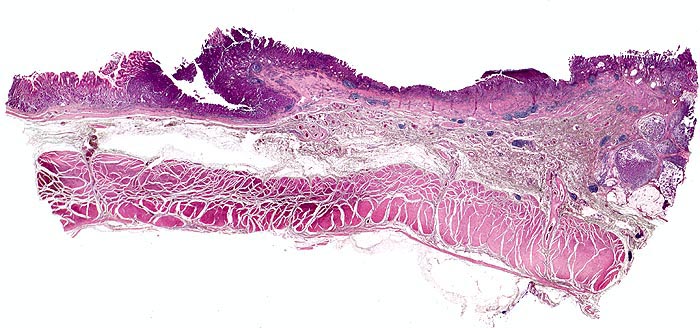

Magenfrühkarzinom

Das Karzinom befindet sich am rechten Bildrand. Der expansiv wachsende Tumor infiltriert die Submukosa. Die Lamina muscularis propria wird nicht infiltriert. An der Basis zeigt das Karzinom eine ausgeprägte Schleimbildung.

Polypoider Tumor im Magenantrum.

Magenfrühkarzinome sind auf die Mukosa (Mukosatyp) bzw. Submukosa (Submukosatyp) beschränkt entsprechend einem Stadium pT1.